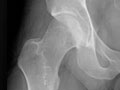

Extremity X-Ray

An extremity X-ray is a picture of your hand, wrist, arm, foot, ankle, knee, hip, or leg. It is done to see whether a bone has been fractured or a joint dislocated. It is also used to check for an injury or damage from conditions such as an infection, arthritis, bone growths (tumors), or other bone diseases, such as osteoporosis.